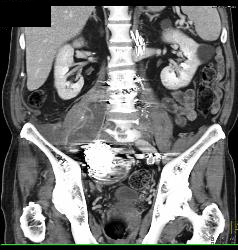

Iliac Artery Aneurysm With Iliopsoas Bleed